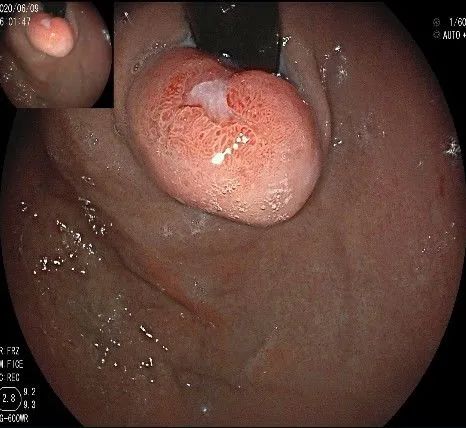

我们的思路:病变长径约2.0cm,位置活动,倒镜后先在胃底侧粘膜下注射,使病变向食管腔方向抬举,然后再在食管腔内做粘膜下注射切开,以获得一个好的术野,果然,注射后粘膜抬举明显,瘤体被挤向口侧。

在食管腔内,瘤体的两侧行粘膜下注射后,在瘤体顶部纵向自口侧向肛侧切开食管粘膜。

向下一直切开至齿状线处,白色为鳞状上皮,红色为腺上皮,颗粒样的部分,就是炎性息肉。切开后可见瘤体为白色,表面有血管网,质地较韧。